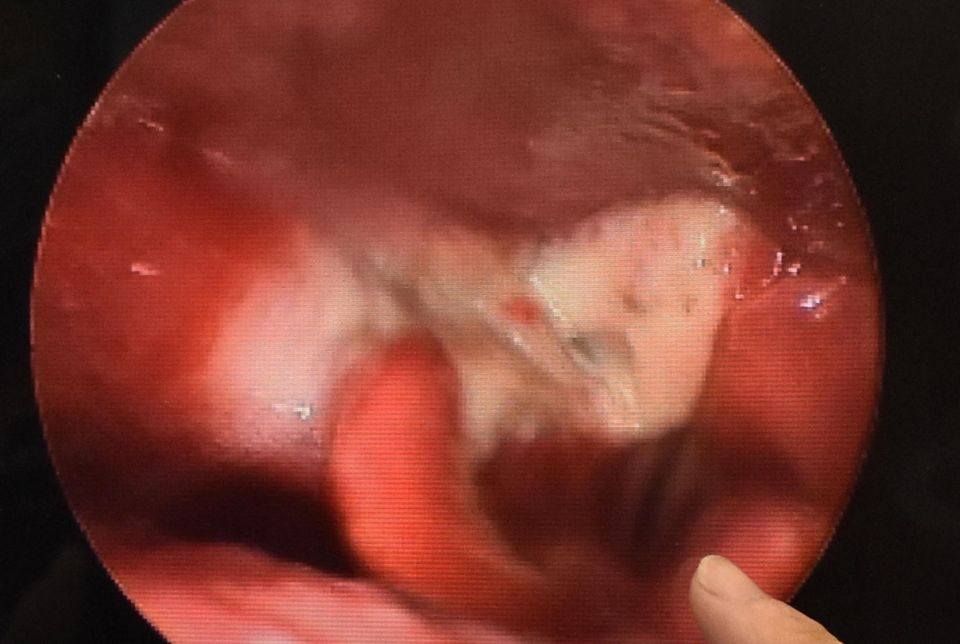

彰基耳鼻喉暨頭頸部主治醫師洪雲聰表示,病人因為比較年輕且沒有喝酒,原以為是比較輕微的喉球症患者,後來發現病人的咽喉部有一巨大的腫瘤,腫瘤本身已經擋住食道的入口,並且部分阻塞聲帶,好在病人來得早,還沒有完全阻塞上呼吸道,不然可能需要緊急做氣切,腫瘤切片結果顯示為「下咽癌」,病人也進一步接受徹底的癌症手術治療,目前手術後恢復良好,並且持續在耳鼻喉科門診追蹤。

病人咽喉部有一巨大的腫瘤,腫瘤本身已經擋住食道的入口,並且部分阻塞聲帶。(彰基醫院提供)